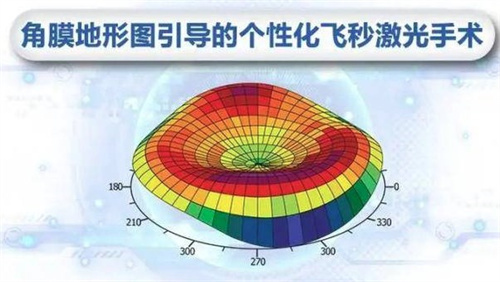

个性化方案:根据患者角膜状况、用眼习惯定制手术,比如喜欢看书或开车的老人,医生会调整晶体参数优化视觉结果。

设备靠前,术前检查超全(OCT、角膜地形图等)。